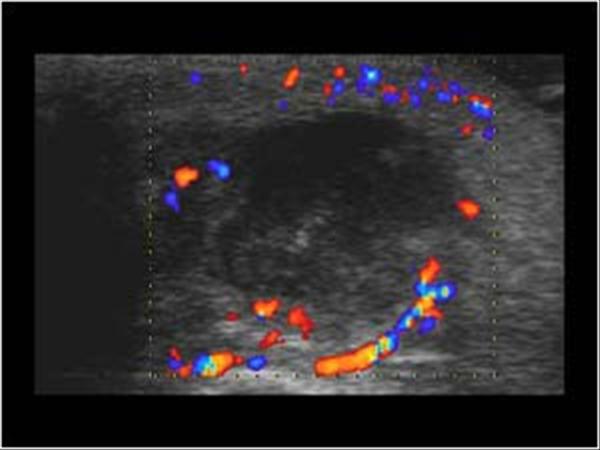

» Thông tin: Nam giới – 36 tuổi.

» Lâm sàng: Sưng đau vùng mang tai.

# Viêm tuyến nước bọt mang tai apxe hóa / Tăng kích thước hạch vùng cổ.